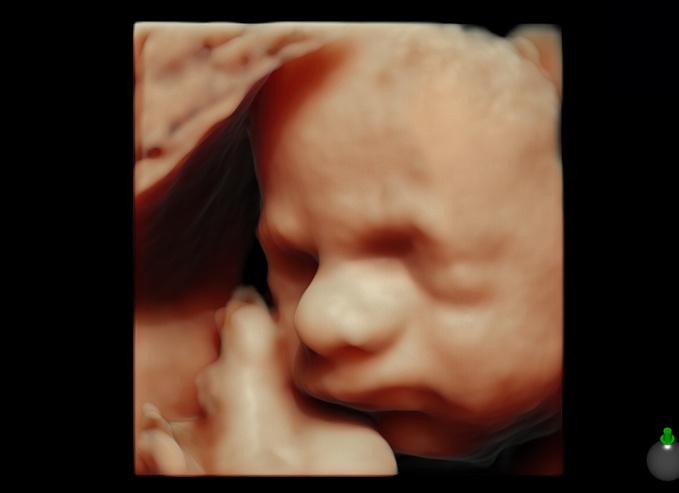

Развитие малыша, как выглядит плод

Посещать врача на 30 неделе беременности надлежит регулярно раз в две недели. Плод растет и уже занимает все пространство. Рост ребенка достигает 35 сантиметров. Двигаться внутри матки ему становиться все труднее, так как он занимает все пространство.

- Жировая ткань ребенка заметно увеличивается, что дает возможность ему даже при преждевременных родах быть защищенным. Кожа малыша пока еще сморщена и имеет красноватый оттенок. Волосики или пушок лануго на теле постепенно уменьшаются, многие малыши так и рождаются с этим пушком. На голове же пушок не пропадает.

- Внутренние органы начинают слаженно работать, головной мозг почти полностью формируется, сердце бьется четко и ритмично.

- Матери в это время опять назначают ультразвуковое обследование, чтобы выявить положение плода, его активность, проверить легкие, движения которых четко просматриваются на УЗИ.

- Глаза малыша на 30 неделе развития широко открыты, он уже умеет морщиться, пожимает плечиками, очень чутко реагирует на звуки, отличает материнский голос от отцовского.